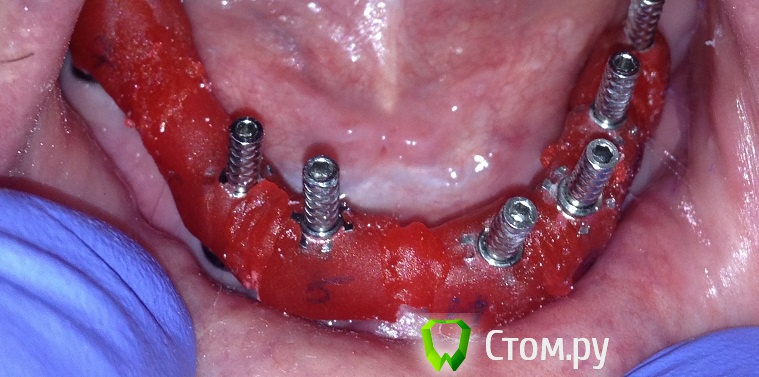

Evikrol Опубликовано 14 мая, 2014 Поделиться Опубликовано 14 мая, 2014 Как эта пластмасса называется, красная которая на трансферах? И склеивали во рту чем? Ссылка на комментарий

MaxDok Опубликовано 14 мая, 2014 Автор Поделиться Опубликовано 14 мая, 2014 Как эта пластмасса называется, красная которая на трансферах? И склеивали во рту чем?Pattern Resin , соединял во рту им же . Ссылка на комментарий